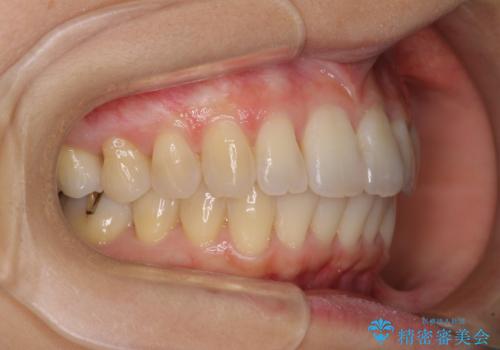

- 前歯の捻れと、それに伴う口元の突出感を気にして来院された患者様です。

早く治療を終えたいとのことで、ワイヤー装置による矯正治療を行うこととしました。

ゴムかけを頑張っていただいたので、当初の予定通り、1年強で治療を終えることができました。